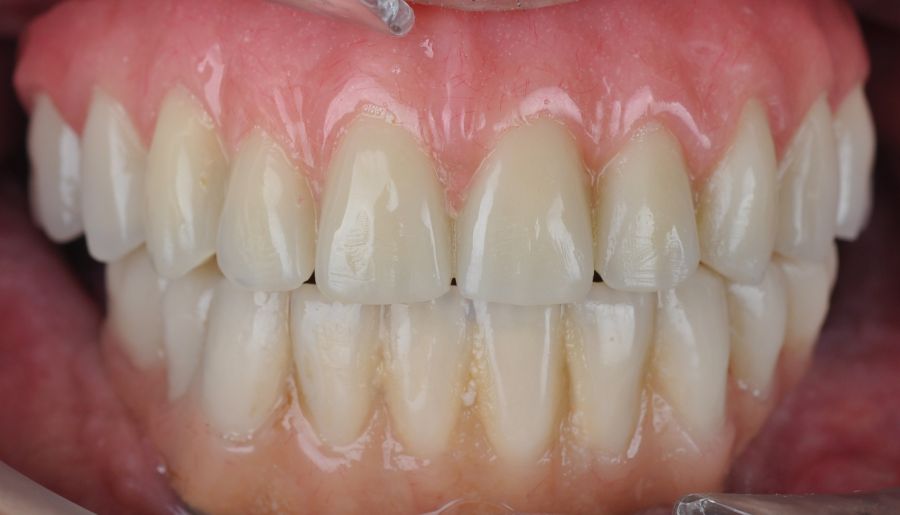

Two months later, with the soft tissues healed around the connections (Figure 16), a new intraoral scanning was made of the implants and the provisional prosthesis for future restoration. A FRI type passivity test (rigid impression splint) was manufactured with an aluminium structure to assess the correct fit on the implants (Figure 17). For implant-supported rehabilitation, a sintered structure was made in chrome-cobalt with machined bases covered with acrylic resin teeth from Bredent® (Figures 18-21).